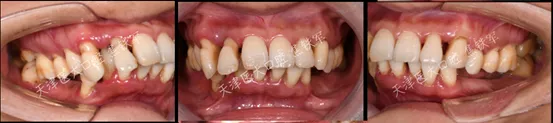

治疗前

口内检查

· 下颌多颗后牙缺失 ,上下前牙成扇形排列,余留牙除上中切牙 1度松动外,其余牙均2-3度松动。

· 面部对称、三等分,面中线与中切牙中线不一致,高位笑线,上下唇无法自然闭合。

· 上唇丰满度:过度,鼻唇角80 °(鼻唇角正常范围:90 °-105 °),上下唇超出美学E线,凸面型;